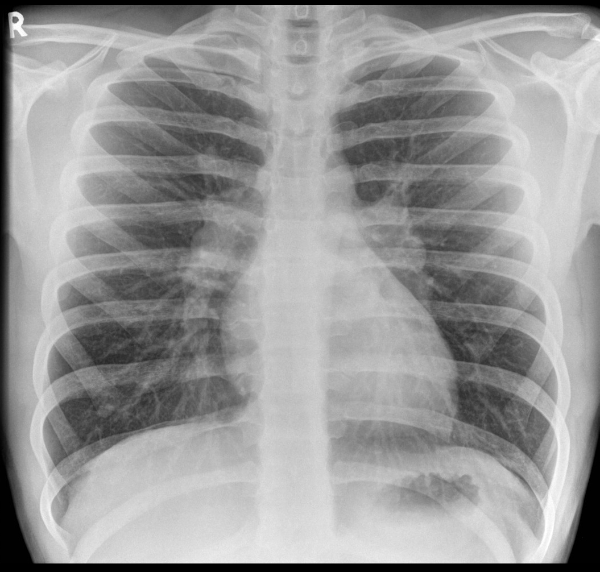

Which 4 features are shown?

2, 4, 5, 8

Note collapse of left lower lobe also, probably due to mediastinal shift – this appears as a triangular area of increased density behind the hear